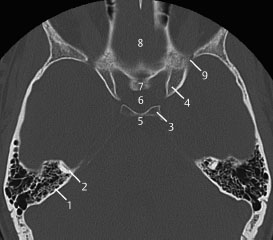

5 internal occipital protuberance. 4 mastoid air cells. 3 anterior clinoid process.

Ct anatomy of skull base. Blue central skull base csb purple posterior skull base teal anterior skull base asb. Foramina of the skull base and the structures that pass through them.

Cranial foramina for further details. A axial three dimensional reconstructed ct image with color coded overlay shows the skull base sections. Ct anatomy of skull base.

The base of the skull is perforated by numerous foramina which allow vessels and nerves to pass through the base of the skull allowing the intracranial cavity to communicate with the rest of the body see main article. Skull ct anatomy the sagittal suture is the line where the right and left parietal bone are in contact. A noncontrast sinus or skull base ct which covers the mastoids temporal bone and entire skull base is recommended and intravenous contrast is not usually necessary as the mri will provide soft tissue detail.

Ct is more sensitive in detecting fibro osseous skull base lesions calcification and sclerosis. The module interface is meant to mimic a radiology workstation with adjacent image scrolling via arrow keys and or mouse wheel button. Navigating the skull base identify the petro occipital fissure to navigate the major structures of the skull base.